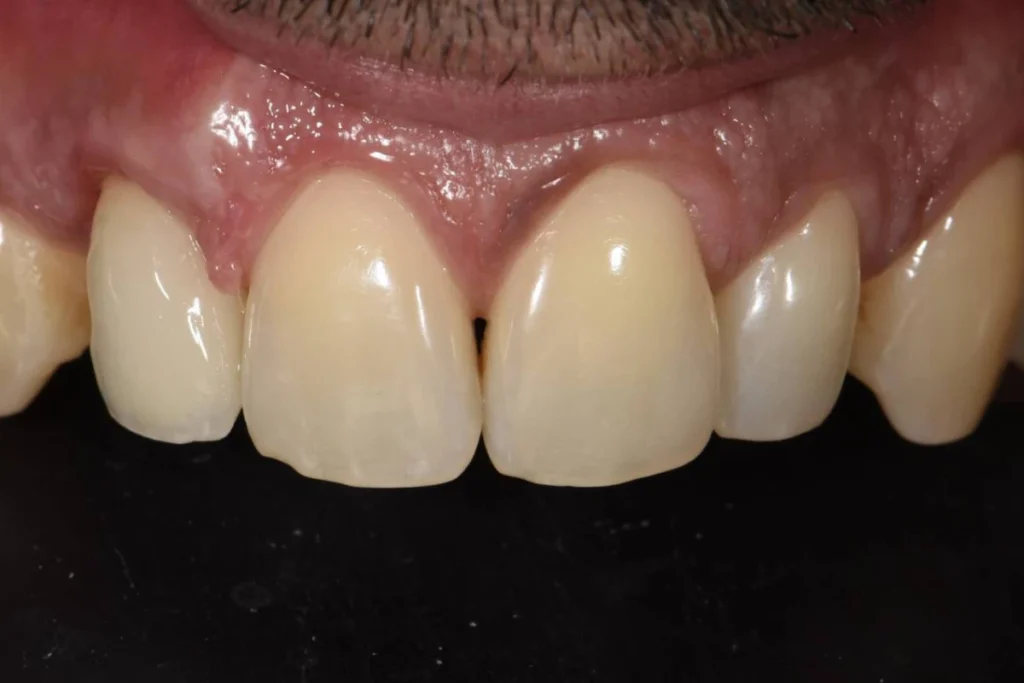

L’intervention est réalisée sous anesthésie locale et doit être complètement indolore. Le patient est revu 3 mois après l’intervention pour prendre une empreinte. Le patient est invité à se rendre au laboratoire de prothèse situé dans le 17ème afin de discuter de la forme de la dent avec l’artisan céramiste. Dans le cas présent, il souhaitait conserver l’écart existant entre ces incisives afin de conserver l’identité de son sourire.

Lors de cet entretien, le prothésiste enregistre également toutes les données de teinte et d’état de surface des dents adjacentes afin de faire la parfaite illusion d’une dent naturelle.

Environ une semaine après la prise de l’empreinte, un essayage est réalisé au cabinet. Si tous les paramètres esthétiques et fonctionnels sont validés, la couronne est posée dans la foulée.

Il est parfois nécessaire de prendre le temps d’une retouche au laboratoire afin d’obtenir le rendu escompté.